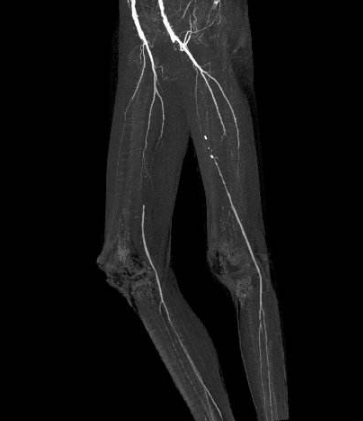

脈管炎圖片

A:血栓閉塞性脈管炎最好發於下肢,表現是肢體的涼、麻、疼,到晚期可以出現靜息痛,嚴重的可以出現足趾和足潰瘍、壞疽,以及肢體的壞死,可導致截肢的風險。血栓閉塞性脈管炎可以發生全身其他臟器的血管,如腎動脈,也可以發生血栓閉塞性脈管炎。早期可以導致……

A:脈管炎的前兆取決於發生的部位和血管,如果是下肢脈管炎,早期會出現腳的溫度降低、顏色蒼白,同時有麻的感覺。進一步發展時可以出現間歇性跛行,即跛行1000米或者800米,患者會出現下肢酸脹的感覺,休息後可以緩解,早期跛行距離為800-1000米……